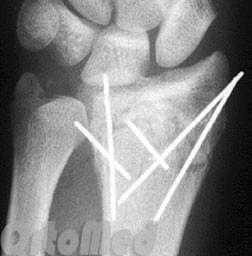

Закрытая репозиция и чрескожная фиксация спицами

Была популярна на протяжении многих лет и продолжает оставаться одним из самых популярных методов в международном масштабе.

Сначала врач закрыто устраняет смещение отломков, затем через отломки в определенных (учитывая характер перелома) направлениях просверливаются спицы.

Плюсы: малая травматичность, быстрота, легкость, дешевизна, отсутствие разреза и как следствие послеоперационного рубца

Минусы: невозможность начала ранней разработки лучезапястного сустава, вследствие чего риск возникновения необратимой контрактуры (отсутствие движений в суставе).

Минусы: концы спиц остаются над кожей, для того чтобы спицу можно было удалить после срастания перелома; риск инфицирования раны и проникновение инфекции в область перелома; длительное ношение гипсовой повязки 1 месяц; невозможность начала ранней разработки лучезапястного сустава, вследствие чего риск возникновения необратимой контрактуры (отсутствие движений в суставе).